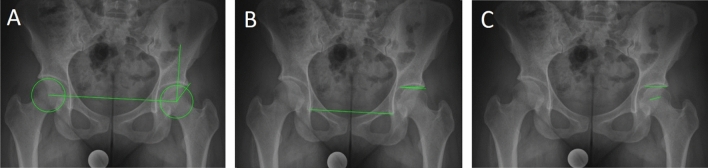

To validate the GAA, standardized a.p. pelvic radiographs of 20 asymptomatic patients were analyzed as previously decribed15. Those patients were treated for an unrelated trauma in our hospital in May 2020. In addition to the GAA, the LCEA23, the acetabular index (AI)24, and the FEAR index15 (Fig. 2) were measured by two independent orthopaedic surgeons (A.Z., J.L.) using the software mediCAD (mediCAD Hectec GmbH, Altdorf, Germany).

Figure 2.

Radiographic Measurements. (A) Lateral Center–Edge Angle: calculated by drawing a best-fit circle around the inferior and medial margins of the femoral head. The angle is measured between 2 lines drawn from the center of the circle, one running vertically along the longitudinal axis of the pelvis and the other running along the acetabular sourcil edge23. (B) Acetabular index: measured by drawing a horizontal line parallel to the transverse pelvic axis, at the most medial edge of the sclerotic sourcil, and then making a second line extending from the medial edge to the most lateral aspect of the sourcil24. (C) Femoroepiphyseal acetabular roof index: formed by 2 lines connecting the acetabular roof inclination and the femoral head physeal scar15.